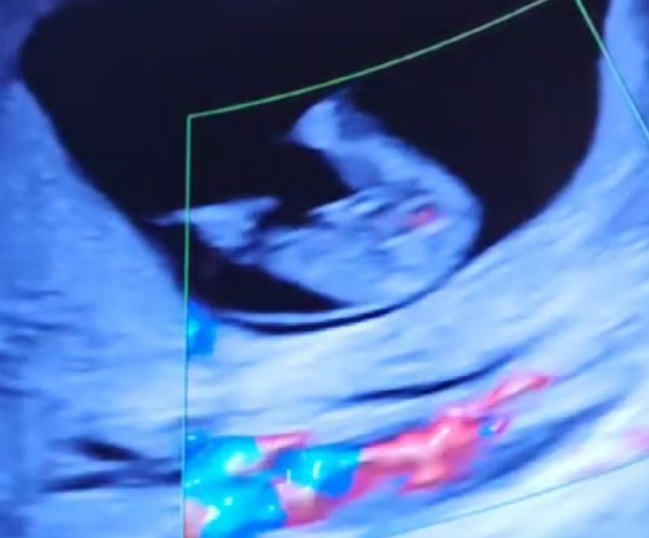

Пол в 14 недель

Пол малышаРешили сходить с мужем на узи в 14 недель, посмотреть на малыша. Об определении пола и мысли не было, но врач неожиданно сказала: «80% девочка. Маловероятно, что мальчик. Не вижу ничего между ног».

Я была уверена, что пол на таком сроке определяют только по половому бугорку, но никак не снизу.

Вот вам для сравнения наш мальчик в 13 недель) там сразу все понятно) у вас скорее всего девочка, действительно ничего не видно между ножек

Качество фото плохое, но если ничего не «болтается» между ног, то похоже девочка

Наша девочка так же выглядела на первом скрининге. У мальчиков реально были писюны, у девочки - ничего. Хотя я тоже не верила, как такое возможно в 12 недель, пишут же что якобы на этом сроке у малышей все одинаково. Но нет )